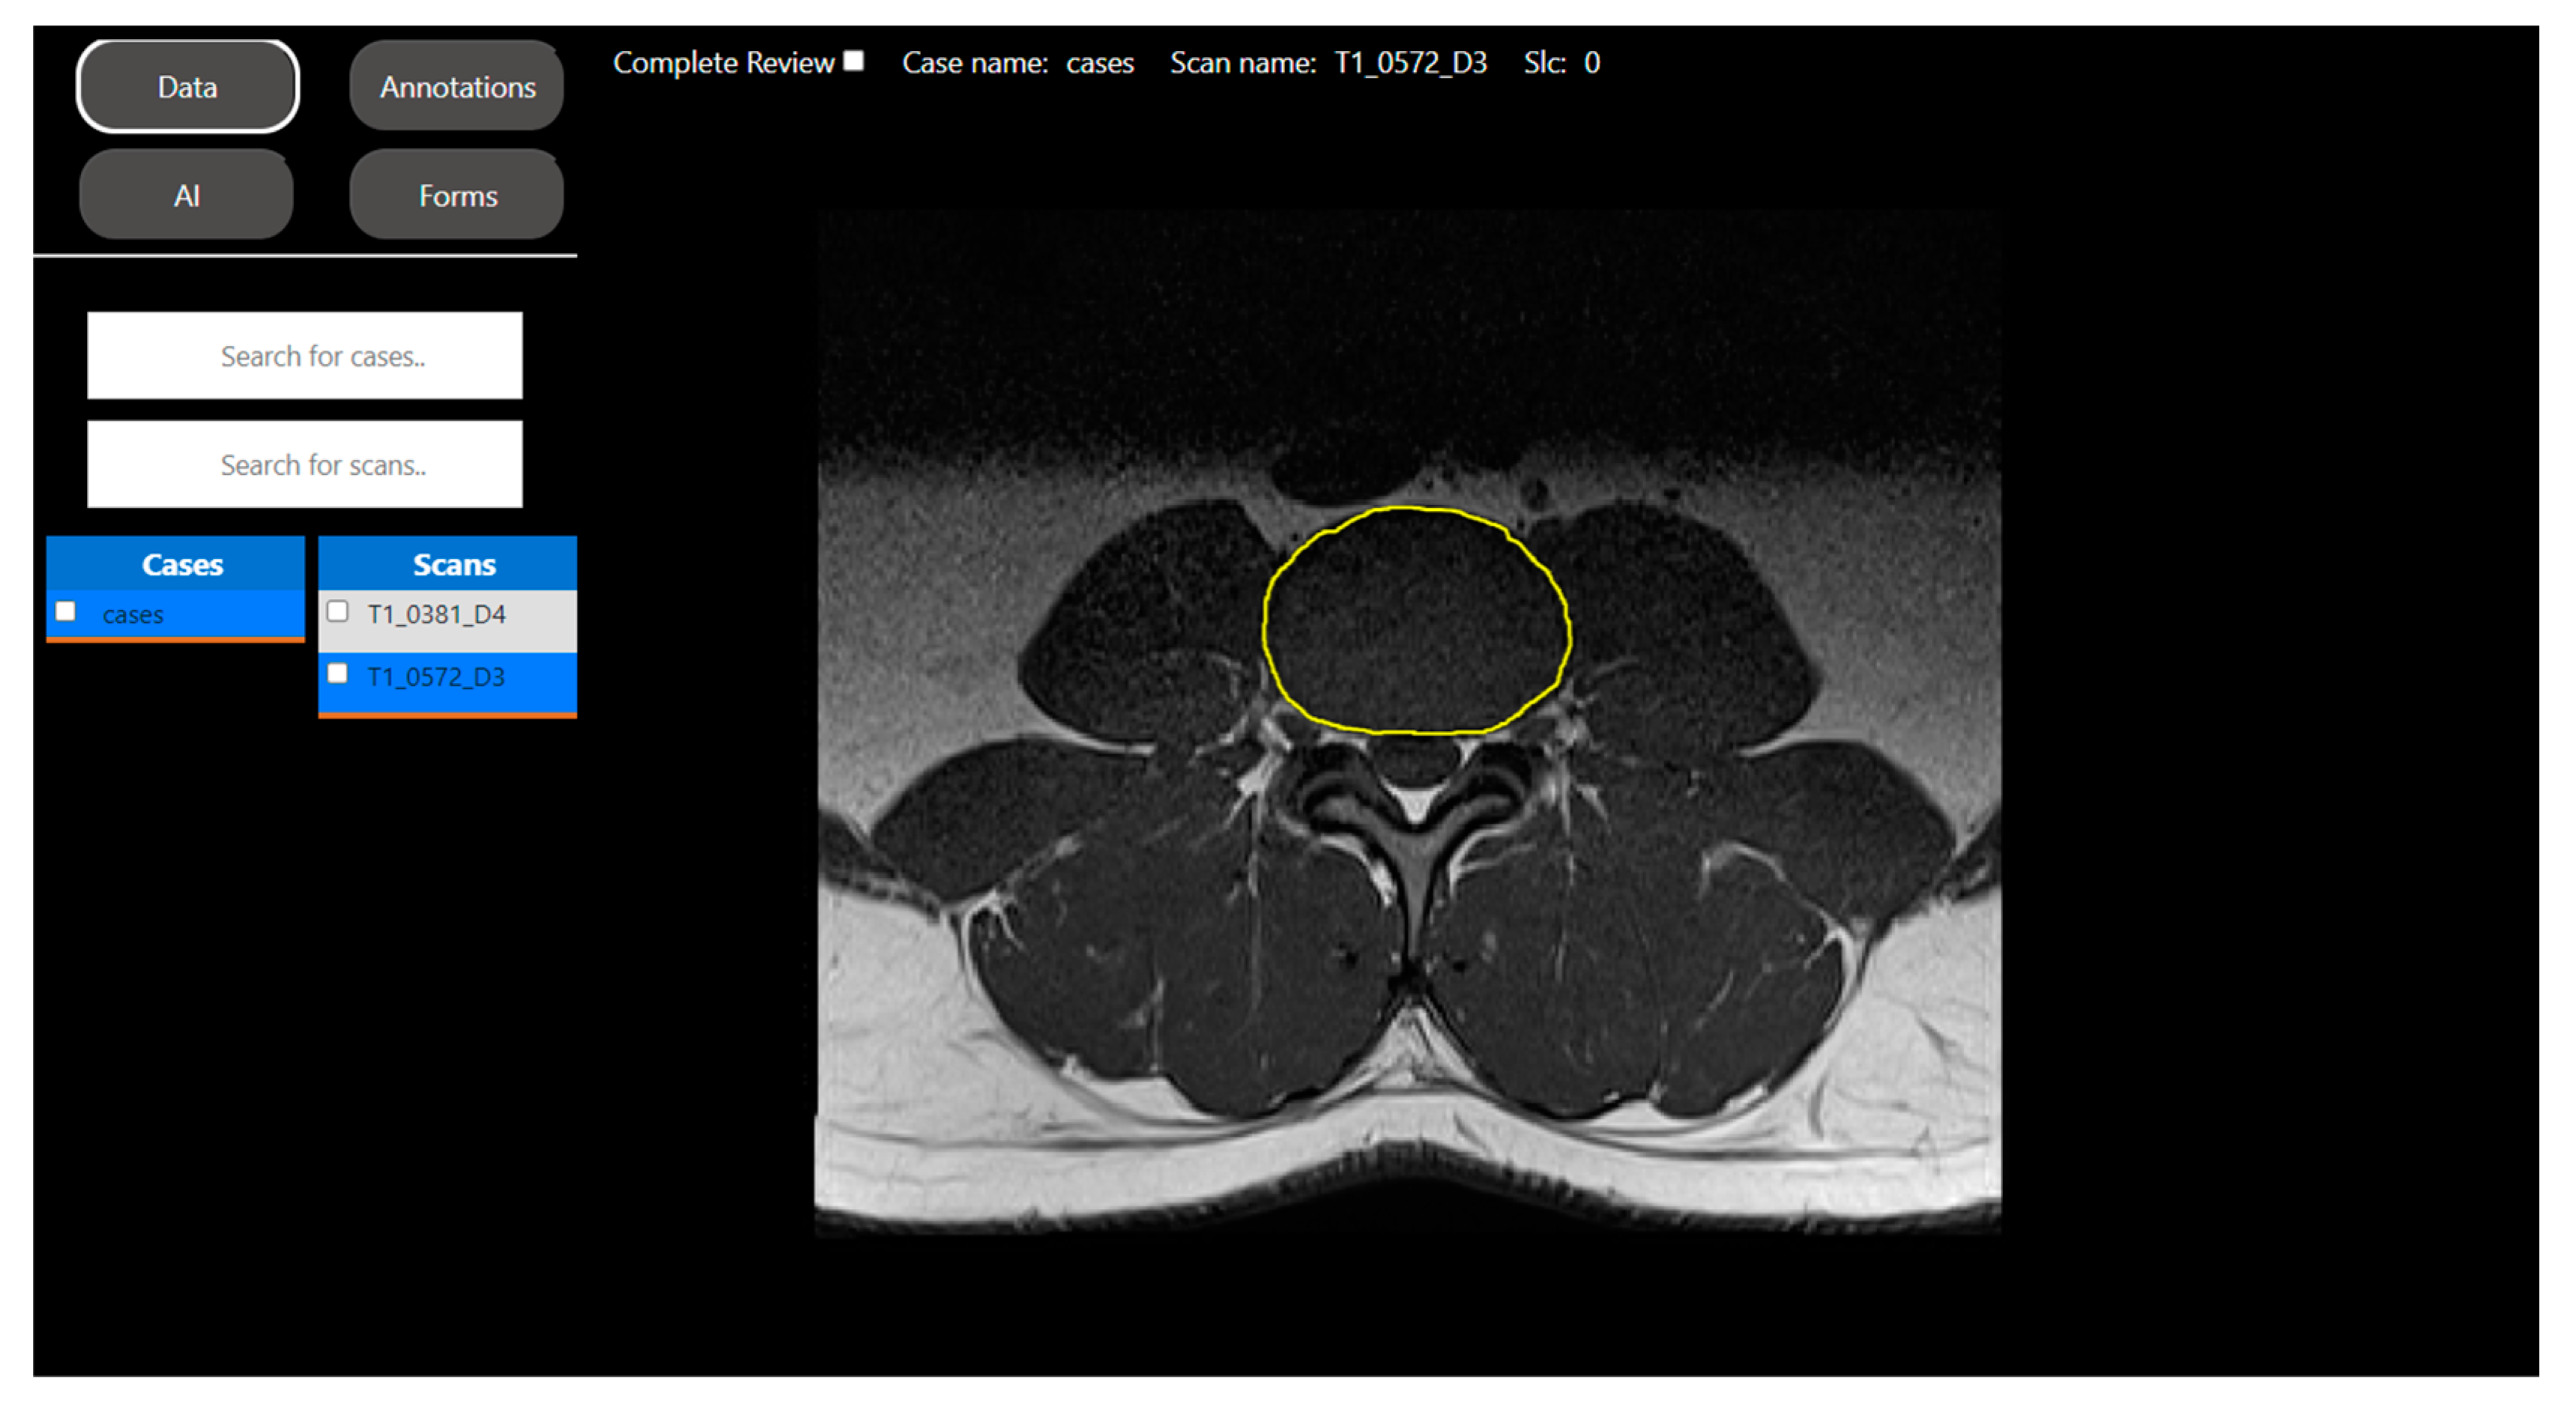

2.2.1. Segmentation Task: Intravertebral Disk Segmentation on T1-Weighted Axial-View MRI Slices

2.2.2. Regression Task: Automated Measurement of Patellofemoral Anatomic Landmarks